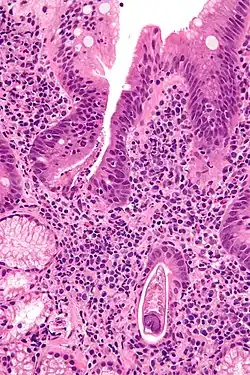

| Micrograph showing strongyloidiasis; a fragment of a worm is seen in the lower right hand corner. H&E stain. | |